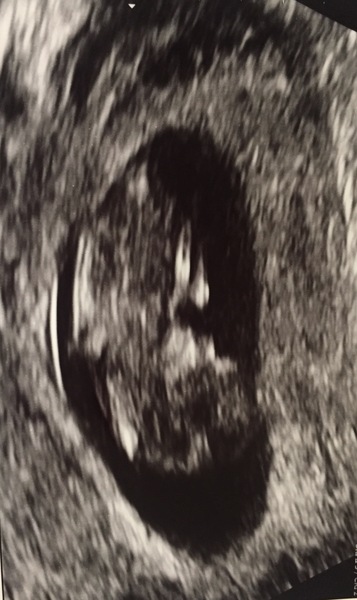

Lovely scan news Mary and Japan and even lovelier that you don't Jane long to wait to see your nippers again!!

I haven't heard anything since my scan last Monday so I'm pretty sure that means I am low risk for all the chromosomal issues and just have to wait for the results in the post now - they said they would phone me by yesterday if high risk. More waiting but I'm hopeful!!